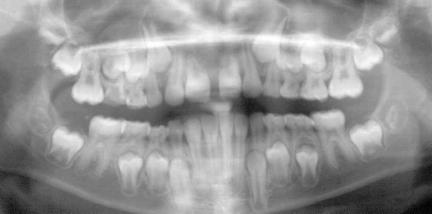

2.) Das Orthopantomogramm (OPG) oder auch Panorama-Übersichtsaufnahme zeigt den Stand des Zahnwechsels, die Zahnanlagen im Kiefer, Fehlbildungen der Zähne, den Zustand der Zahnwurzeln und des Zahnhalteapparates (Parodont).

Insbesondere beim Wechselgebiss gibt das Röntgenbild dem Zahnarzt und Kieferorthopäden die erforderlichen Informationen über die Anlage und Lage von Zähnen sowie den Entwicklungsstand der Wurzelbildung. Hier können auch rechtzeitig besondere Befunde wie Nichtanlage von Zähnen, überzählige Zähne und falsch liegende Zähne (Retentionen) entdeckt werden.

Diese Aufnahmen werden während der Behandlung wiederholt, um z.B. den Zahnwechsel zu kontrollieren, die Zahnachsenstellung zu überprüfen und Veränderungen am Zahnhalteapparat und der Zahnwurzel zu sehen.

Wechselgebiss